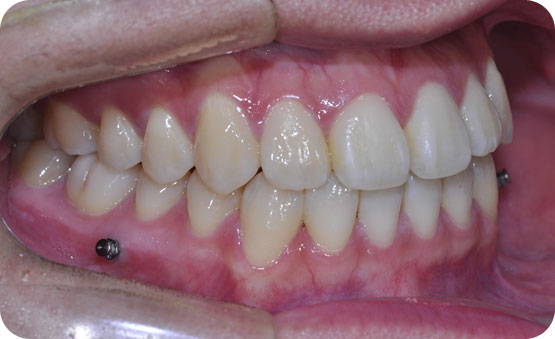

하악 구치부 손실 부위의 사랑니 견인으로 배열

Before

After